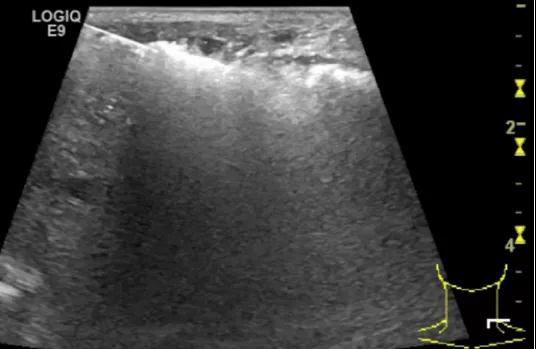

第四例是胸腺癌化妆包,术后、化疗之后淋巴结转移,肿块范围巨大,99mm*61mm,边界不清,呈浸润状,肿块包绕颈动脉,颈内静脉压闭,症状明显。由于患者放化疗也不敏感、血供非常丰富,于是采取多点姑息性消融。姑息性消融后未实现完全消融,病灶大片坏死,肿胀疼痛得到明显的缓解,后续患者未再来复查。

(病例4图例)